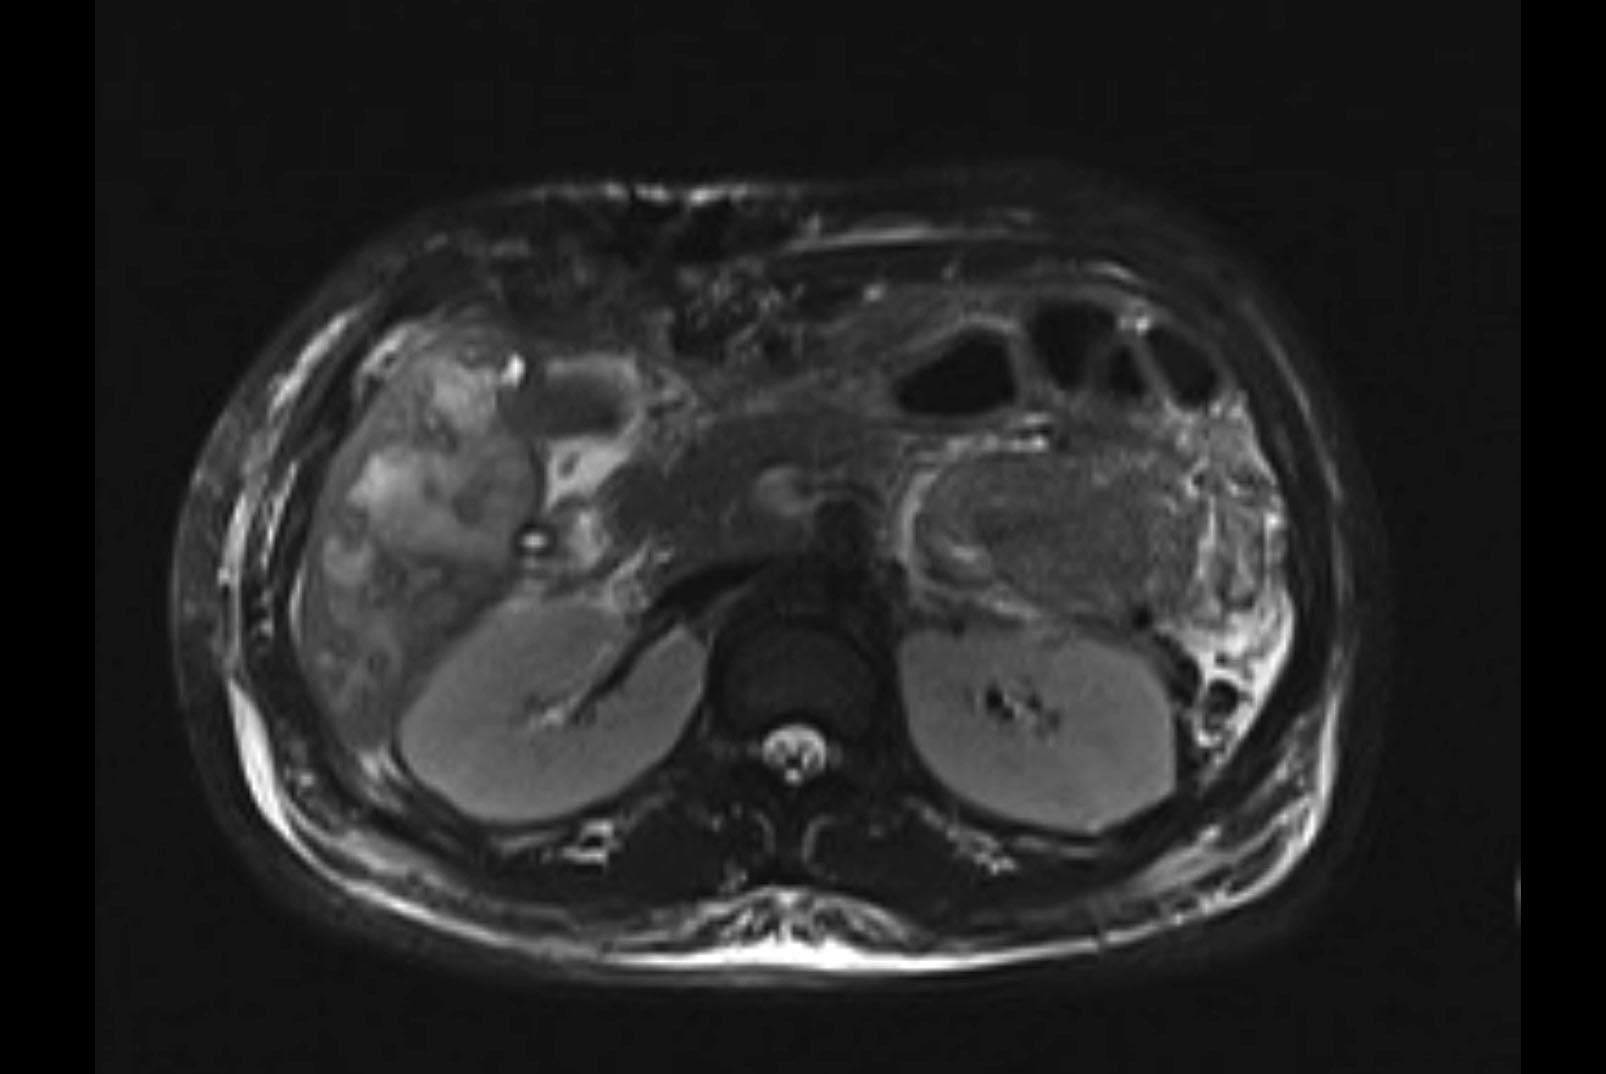

MRI T1

Imaging analysis

Based on initial findings, which issue(s) would you be most concerned about?